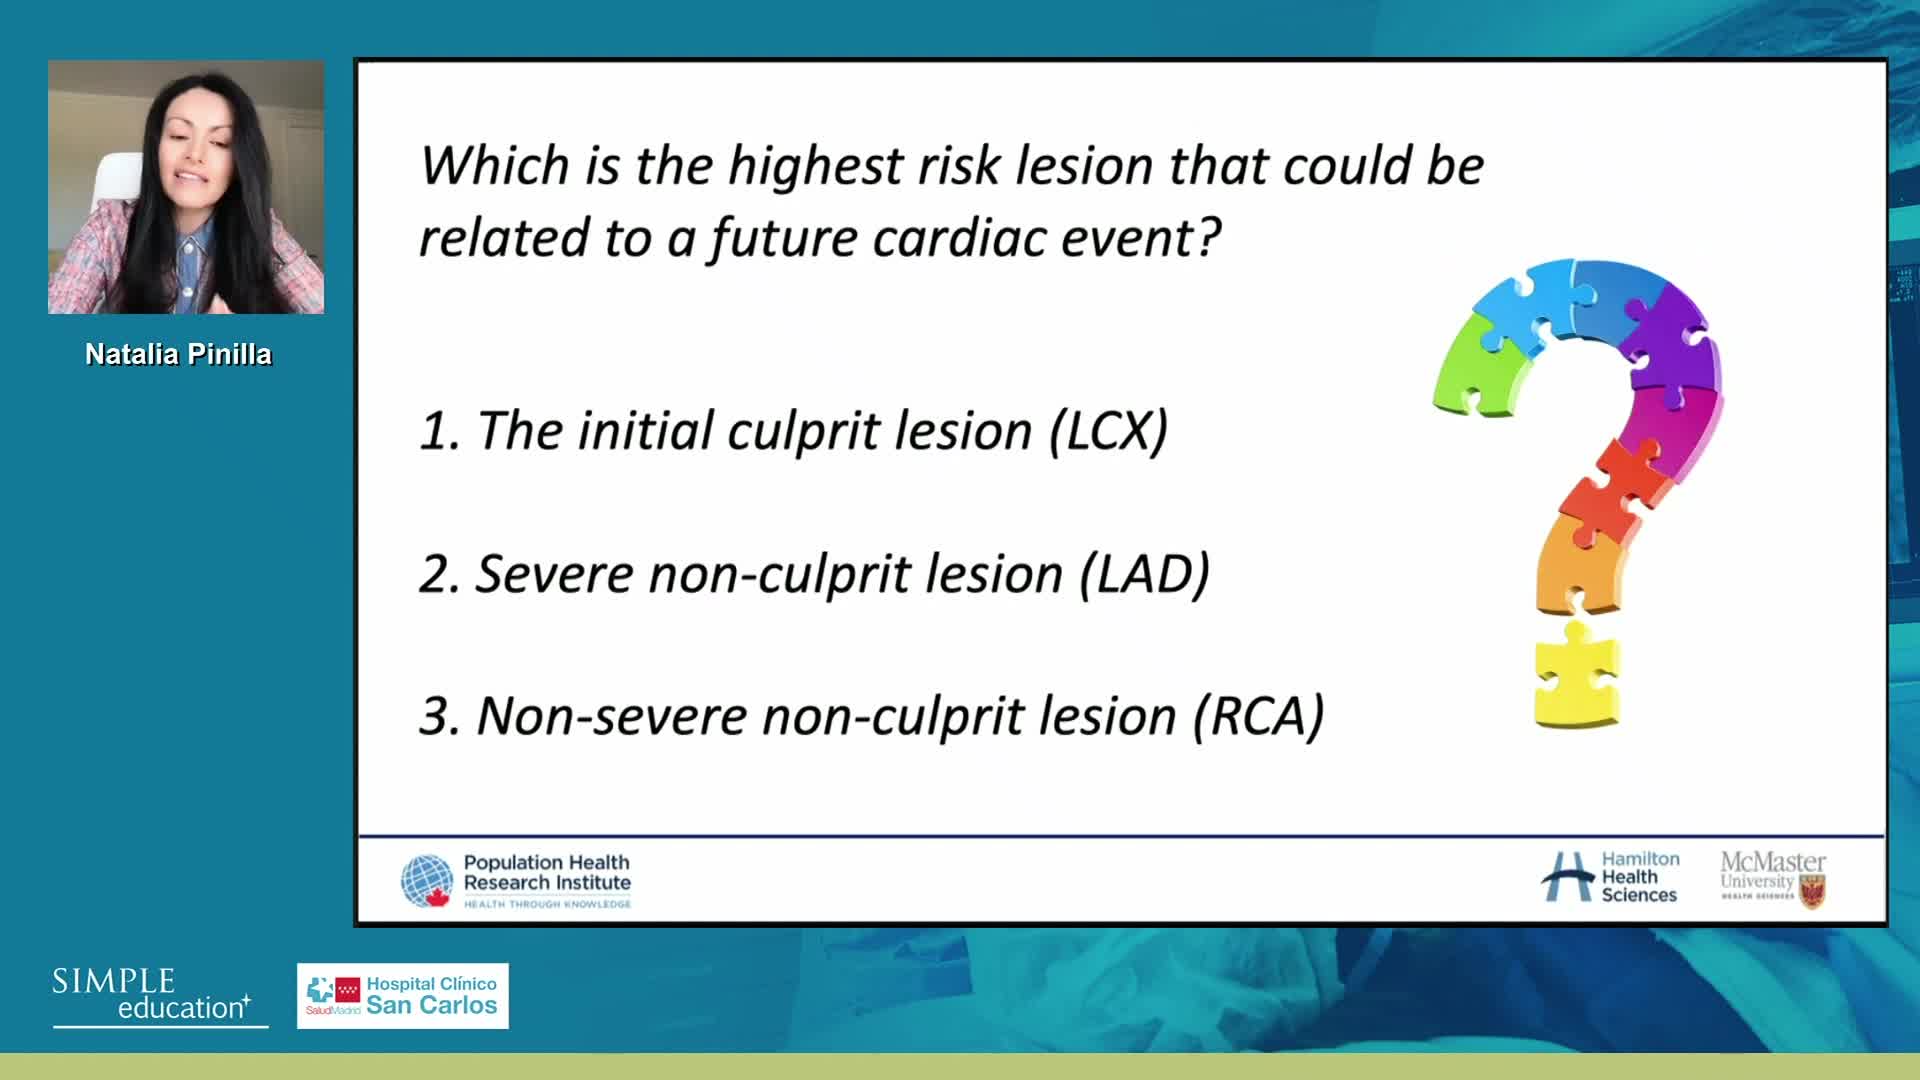

Spotlight Discussion: Management of multivessel disease in patients with acute coronary syndromes

Intracoronary guidance in acute coronary syndromes - Dr Hernan Mejia-Renteria